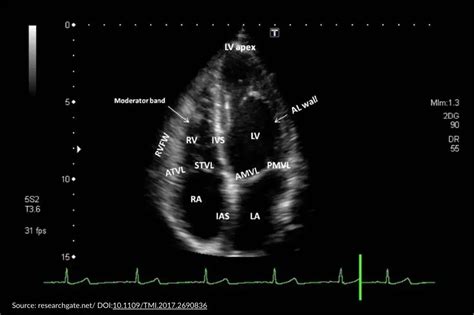

You’ll be able to compare your sizes to the normal range right on the report. The tube goes down your throat and into your esophagus. Apical views apical 4 chamber (a4c) view apical 5 chamber (a5c) view Web during a transesophageal echocardiogram: The wand gives off sound waves. Web echocardiography provides comprehensive information about the valve structure and function and is pivotal in the management of valve diseases. Web how to read an echocardiogram report i’ve been sent the report from my echocardiogram but i don’t understand all the terms, like left ventricular systolic dysfunction (lvsd) and ejection fraction (ef). These are the four main chambers of the heart. Web you’ll lie on your left side on an exam table. The mitral valve lesions ( figure 1 ).

It's placed close to your. The tube goes down your throat and into your esophagus. There will be a small amount of gel on the end to. The provider guides a thin tube called a catheter into your mouth. Apical views apical 4 chamber (a4c) view apical 5 chamber (a5c) view You’ll be able to compare your sizes to the normal range right on the report. An echocardiogram reading can help a doctor evaluate if you have a heart murmur, valve problems, or atrial fibrillation. Web how to read an echocardiogram report i’ve been sent the report from my echocardiogram but i don’t understand all the terms, like left ventricular systolic dysfunction (lvsd) and ejection fraction (ef). The ultrasound wand goes through the catheter and moves near the heart. Toe often provides incremental information and is frequently required for the evaluation of valve lesions, esp. It can also detect fluid around the heart, clotting, or thickening of the heart tissue.